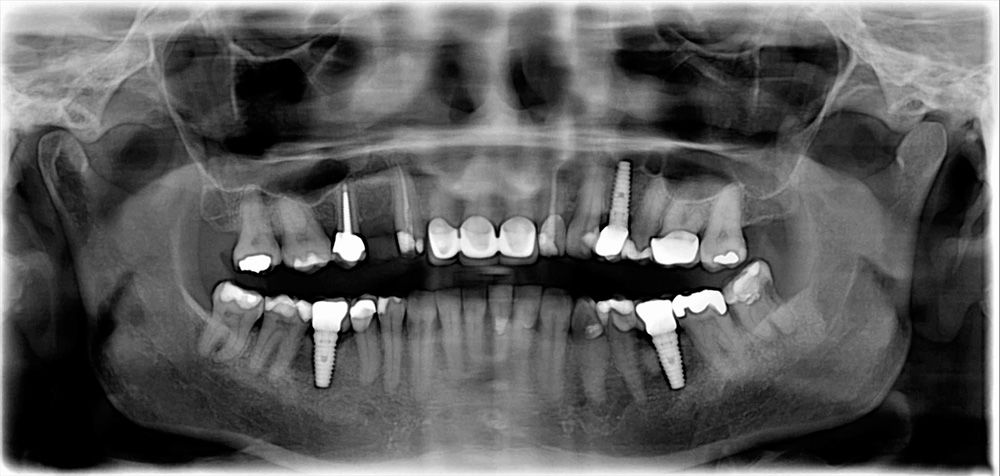

Panoramic xray - Cebu

The Panoramic x-ray, is a two-dimensional (2-D) dental x-ray examination that captures all completely the mouth in a single image this are the following the teeth, upper and lower jaws, surrounding structures and tissues.